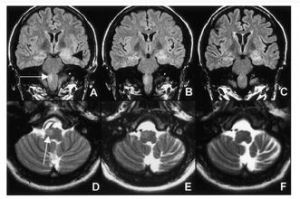

小腦萎縮症確診方法之一,是利用核磁共振成像(MRI)掃瞄腦部,可以見到病變進行中的小腦萎縮。最精確的診斷法,就是DNA分析,可以分辨本症的不同類型。不是所有類型的脊髓小腦萎縮症都會遺傳,所以患者的子女可以接受DNA檢查,以便得悉他們會否有發病的危險。